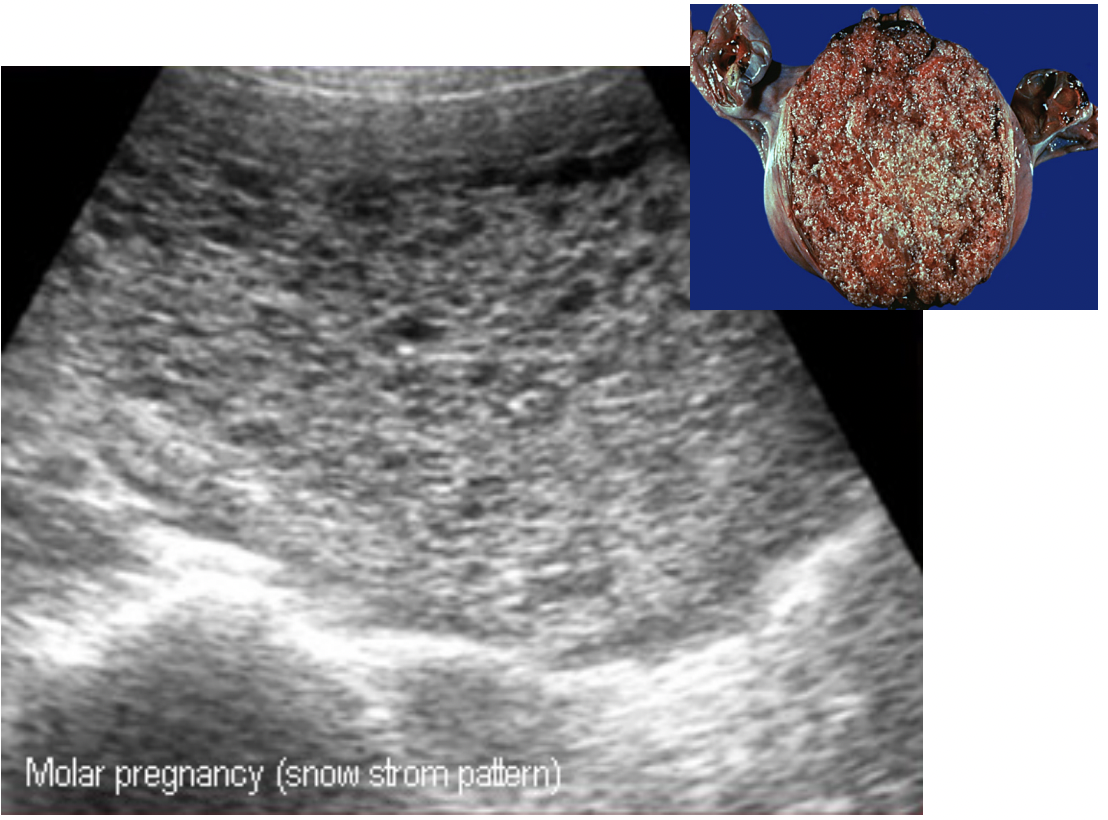

What is a hydatidiform mole?

How can hydatidiform mole be detected prenatally?